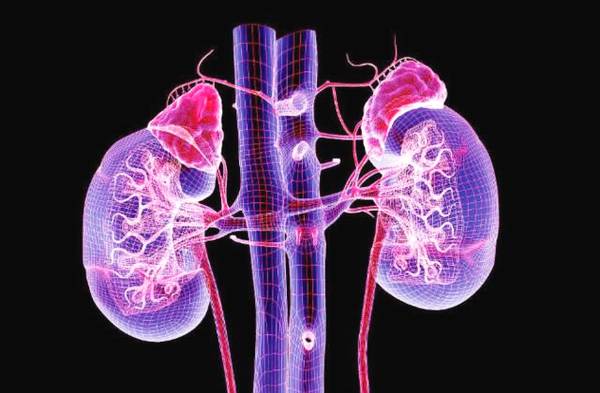

肾形态与位置歌诀

形如蚕豆表面平,脊柱旁列八字形;

被膜肾蒂腹内压,相邻器管都固定;

左肾上平胸十一,右低半椎十二中;

肾门约对一腰椎,病变肾区扣压疼。

肾窦歌诀

肾门向内有间房,多种结构里面藏;

动静肾盂大小盏,淋巴神经和脂肪。

肾被膜歌诀

纤维衬衣脂肪袄,筋膜外罩厚又牢。

肾血液循环歌诀

肾血循环特点三,管粗压高快循环;

入球短粗出球细,滤出原尿不困难;

两级毛细血管网,先滤后吸多完善。